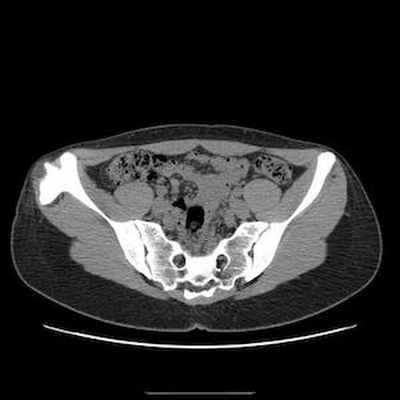

КТ: контур периферического кортикального слоя не прерывается на границе с кортикальным слоем подвздошной кости. Хорошо различимая трабекулярная структура указывает на остеогенный экзостоз.

Свидетельствует о наличии хрящевого обызвествления, захватывающего, по-видимому, соседние мягкие ткани.

TDM Pelvis Axial

TDM Abdomen Axial tissus mous